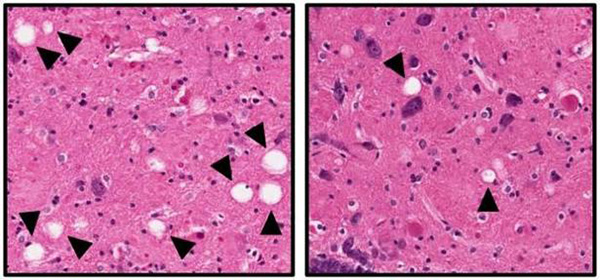

Disminución de muerte neuronal (en blanco) con el fármaco experimental (izquierda)

Nueva York, 07/11/2017 (El Pueblo en Línea) -El alzhéimer es una enfermedad neurodegenerativa causada, según han mostrado infinidad de estudios, por la acumulación en el cerebro de ovillos neurofibrilares de proteína tau y de placas de beta-amiloide, altamente tóxicos para las neuronas. Tal es así que la gran mayoría de investigaciones desarrolladas para prevenir o ralentizar la enfermedad han tenido por objetivo evitar la formación de estos ovillos y placas. Sin demasiado éxito. Pero, ?qué pasaría si se desarrollara una molécula que, en lugar de actuar sobre las placas y los ovillos, protegiera a las neuronas cerebrales? Pues que el afectado conservaría sus funciones cognitivas intactas. De ahí la importancia de un estudio dirigido por investigadores de la Facultad Carver de Medicina de la Universidad de Iowa en Iowa City (EE.UU.), en el que se describe un nuevo fármaco experimental capaz de prevenir la muerte celular de las neuronas cerebrales y, en consecuencia, de evitar el deterioro cognitivo asociado al alzhéimer y los síntomas de la depresión. O así sucede, cuando menos, en modelos animales –ratas, según ABC.

Como explica Andrew Pieper, co-autor de esta investigación publicada en la revista ?BiologicalPsychiatry?, ?hace ya mucho tiempo que se sabe que los cerebros de los pacientes con alzhéimer presentan placas de beta-amiloide y ovillos neurofibrilares de proteína tau anómala, pero todavía se desconoce cuál es su efecto en el proceso de la enfermedad. Nuestro trabajo muestra que mantener las neuronas vivas en el cerebr oayuda a los animales a preservar una función neurología normal con independencia de los procesos patológicos tempranos de la enfermedad, caso de la acumulación de estos ovillos y placas?.